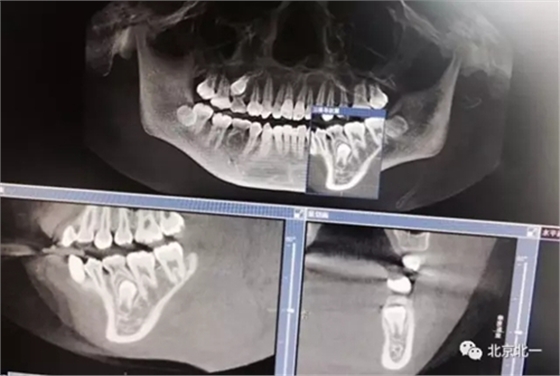

圖一:拔牙前影像片(CBCT)

術(shù)后拍片